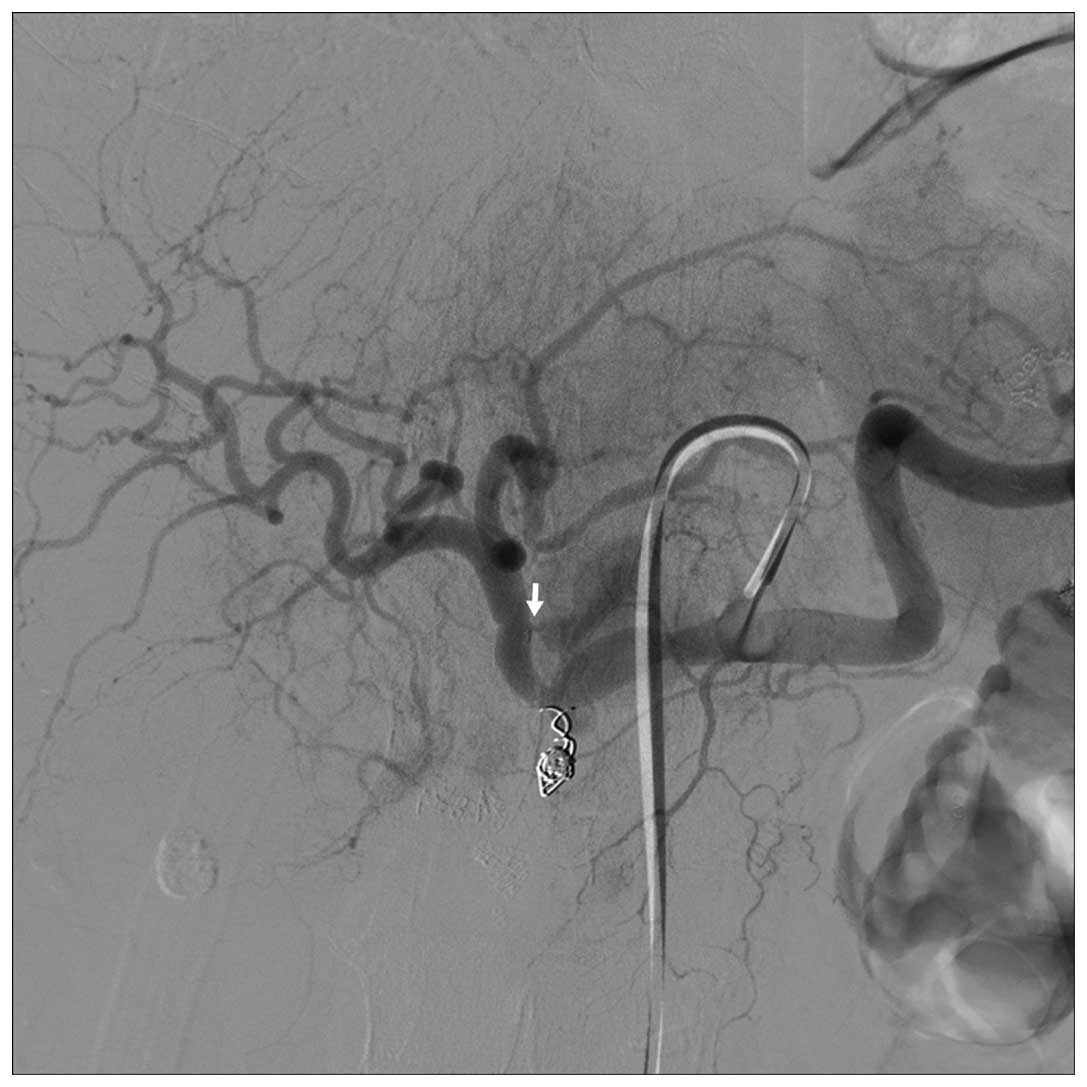

Осложнения при эмболизации простаты - фото презентация